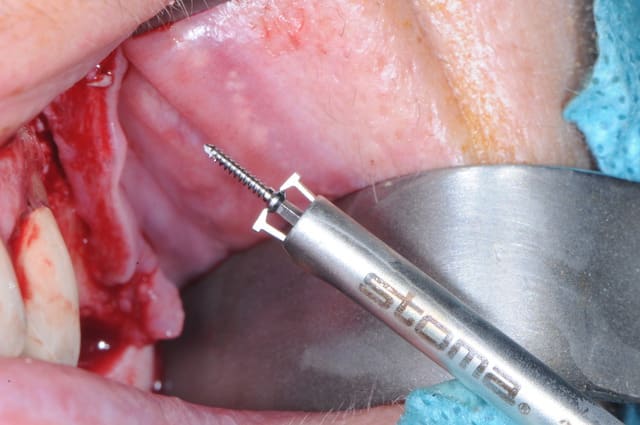

les vis STOMA de 1mm de diamètre j'adore !

ici, avec le sinus lift réalisé avec le DASK (merci Michael B.) et avec la greffe d'apposition j' mis 1h45mm. un vrai bonheur !

la grosse fraise Dask est vraiment superbe, quel gain de temps!